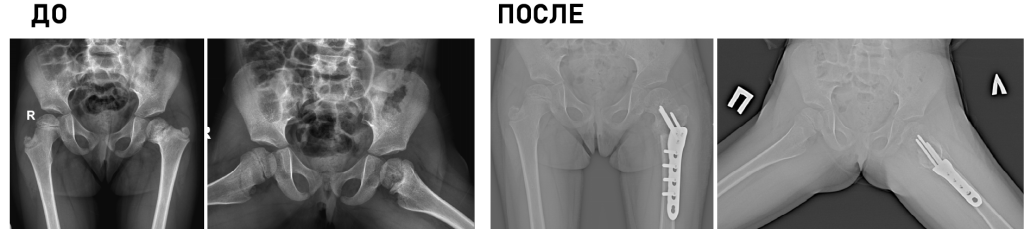

Клиника является единственным медицинским учреждением Российской Федерации, выполняющим полный комплекс диагностических и лечебных мероприятий у детей с деструктивными поражениями любых отделов скелета, в т.ч. малоинвазивные биопсии, иммунологические исследования, гистологическую и бактериологическую верификацию.

Основной принцип работы: обязательный учет возрастных особенностей ребенка и потенциал его роста.

Технические возможности: технологии малоинвазивной (MIS) и реконструктивной хирургии, костнопластические материалы и инструментальная фиксация, современное силовое и ультразвуковое операционное оборудование, навигация, нейромониторинг.